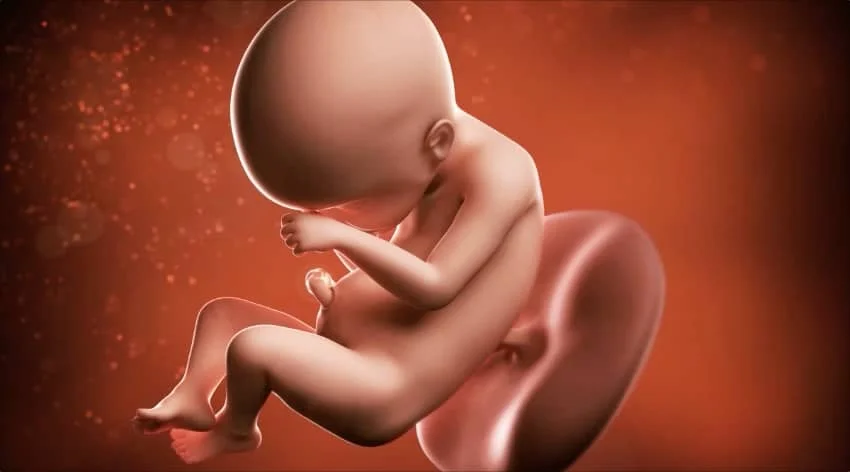

Fetal Development at 24 Weeks

⭐ Fetal Development at 24 Weeks

Size and Weight

At this stage, your baby:

• Weighs about 600–700 grams

• Measures 30–32 cm in length

• Is roughly the size of a large ear of corn or zucchini

Facial and Physical Features

• Eyebrows, eyelashes, and eyelids are well formed.

• Hair growth on the head becomes more noticeable.

• The skin is still thin and slightly wrinkled but gradually thickening.

Lung Development

Week 24 is crucial for lung maturation:

• The air sacs (alveoli) are forming.

• Surfactant production begins—an essential substance for keeping air sacs open after birth.

• Baby practices “breathing” by inhaling and exhaling amniotic fluid.

Nervous System

Neural connections are forming rapidly, allowing more coordinated movements, such as:

• Grasping the umbilical cord

• Touching the face

• Reacting to light and sound

Baby’s Movements

Movements are strong and easily felt:

• Kicks, rolls, stretches, and twisting motions

• Increased activity when the mother is resting

• More predictable wake–sleep cycles (baby sleeps up to 12–14 hours a day)